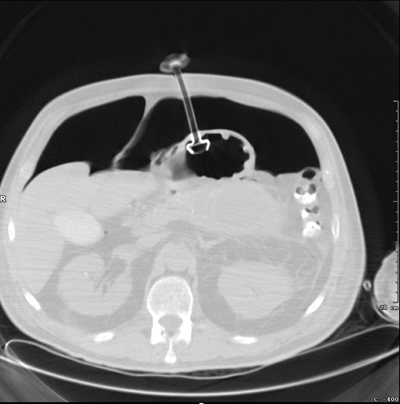

Image of gastrostomy tube with adjacent pneumoperitoneum